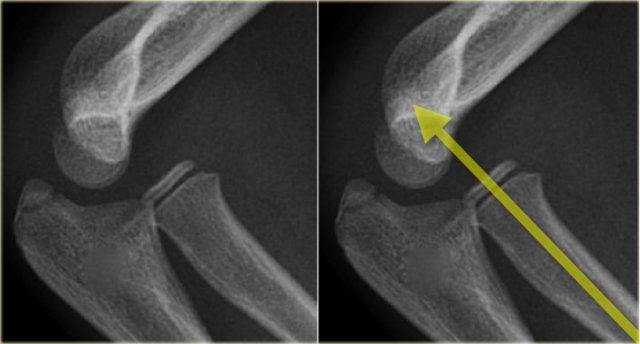

Sự xoay của mảnh gãy tạo ra hình ảnh điển hình trên phim X-quang (mũi tên).

Gãy chỏm con

Trong khi gãy lồi cầu ngoài xảy ra ở trẻ em trong độ tuổi từ 4 – 10 tuổi, gãy chỏm con đơn độc được gặp ở trẻ em trên 12 tuổi.

Gãy xương chỏm con là không phổ biến.